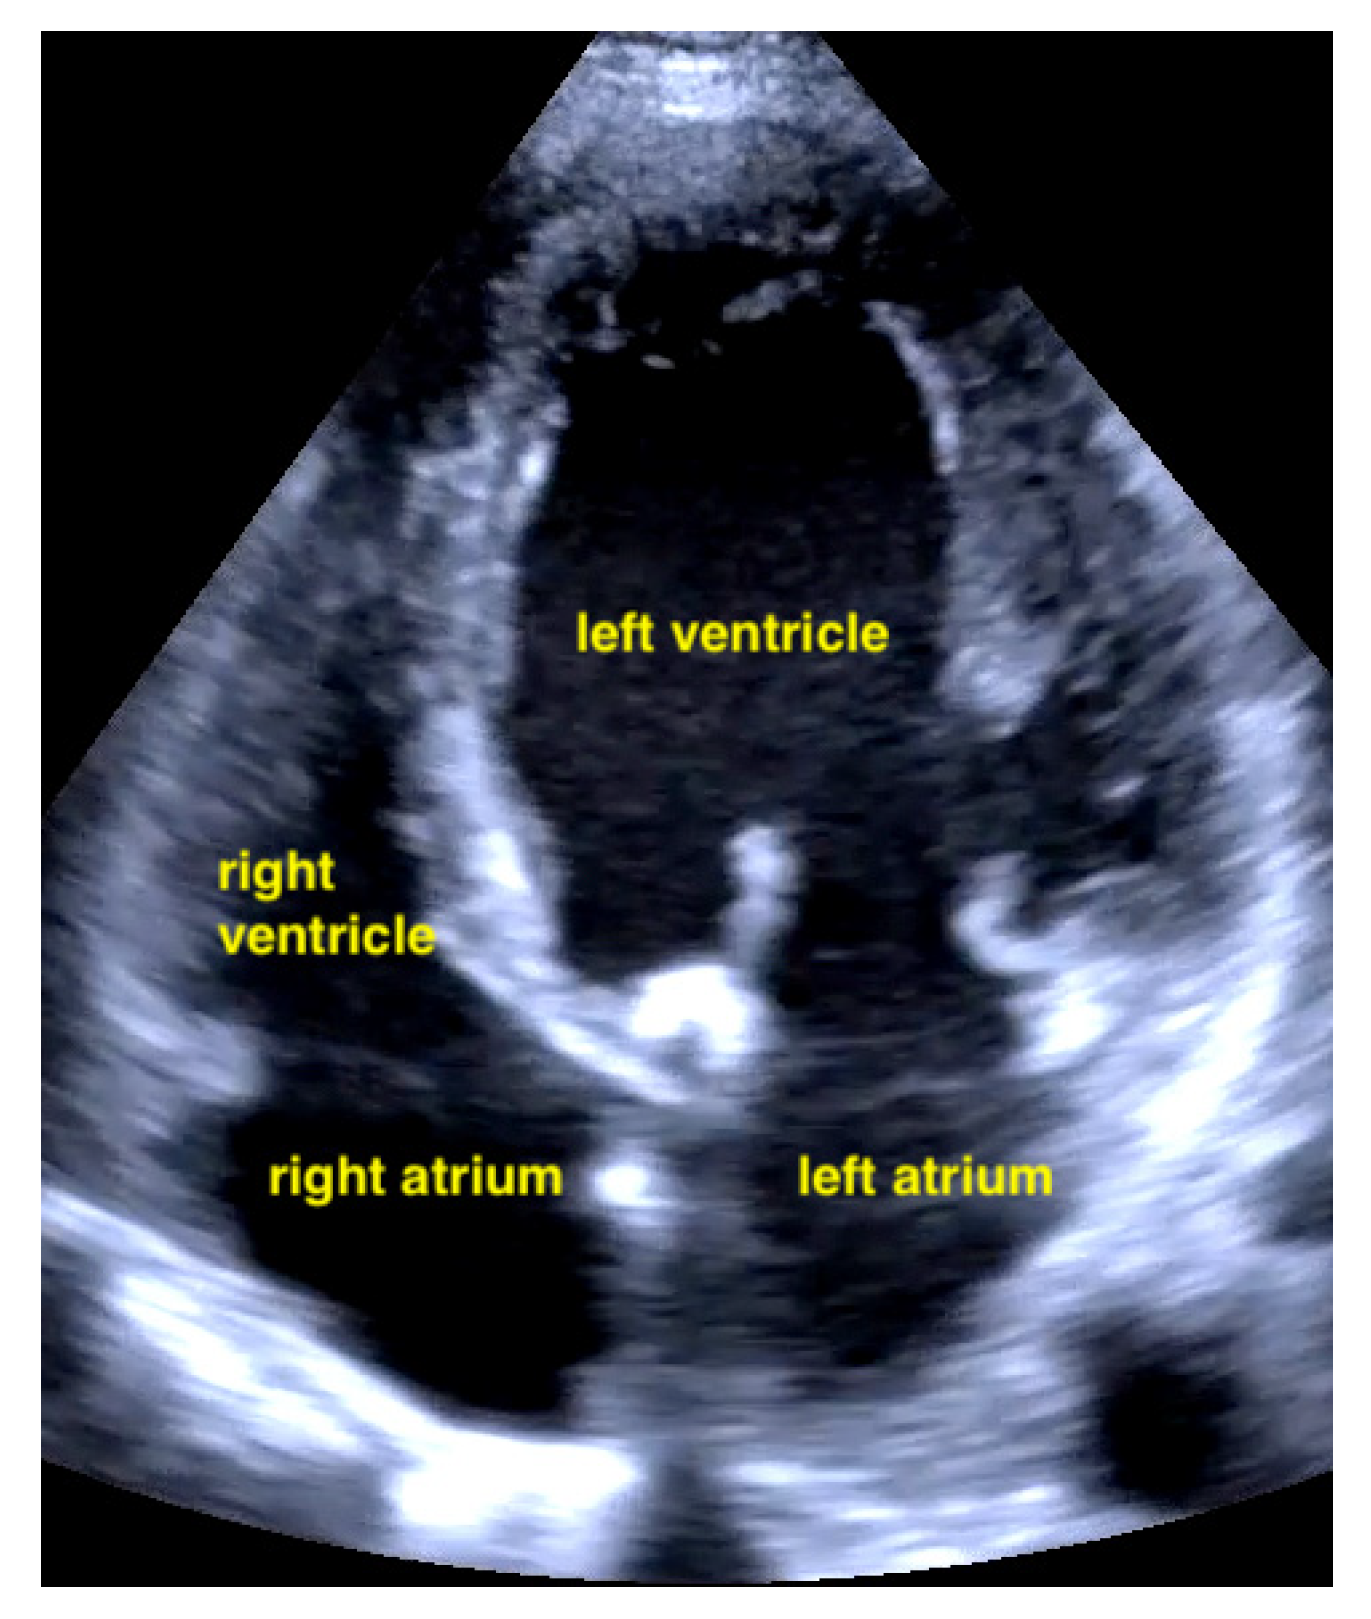

Pericardial effusions are best identified with a convex or sector probe in the subxiphoid or parasternal view. While it is important to simply note whether an effusion is present, sonographic and clinical (hypotension and tachycardia) evidence of cardiac tamponade should be sought. These include diastolic collapse of the right atrium free wall, followed by free wall collapse of the right ventricle as tamponade worsens. Both the apical and subcostal four-chamber views are ideal for this assessment. However, the subcostal window allows for a rapid transition to the proximal IVC view, which is dilated (>2 cm) and does not vary with respiration in cases of cardiac tamponade. Although many cases of medium and large pericardial effusions are obvious on ultrasound, there are notable exceptions. These include some hemorrhagic effusions which show significant coagulation, thus appearing echogenic on ultrasound, leading to frequent confusion with an epicardial fat pad or even a portion of the myocardial wall. Conversely, some epicardial fat pads may be confused with pericardial effusions, especially by novices. Differentiating between the two is easy by using anatomical knowledge. An epicardial fat pad does not extend enough inferiorly to be seen on a longitudinal IVC inlet view, while a pericardial effusion will in virtually all cases (Figure 7, Figure 8, Figure 9 and Figure 10).

Pericardial effusion in apical four chamber view compresses the right atrium slightly (RA = right atrium, LA = left atrium, RV = right ventricle, LV = left ventricle).